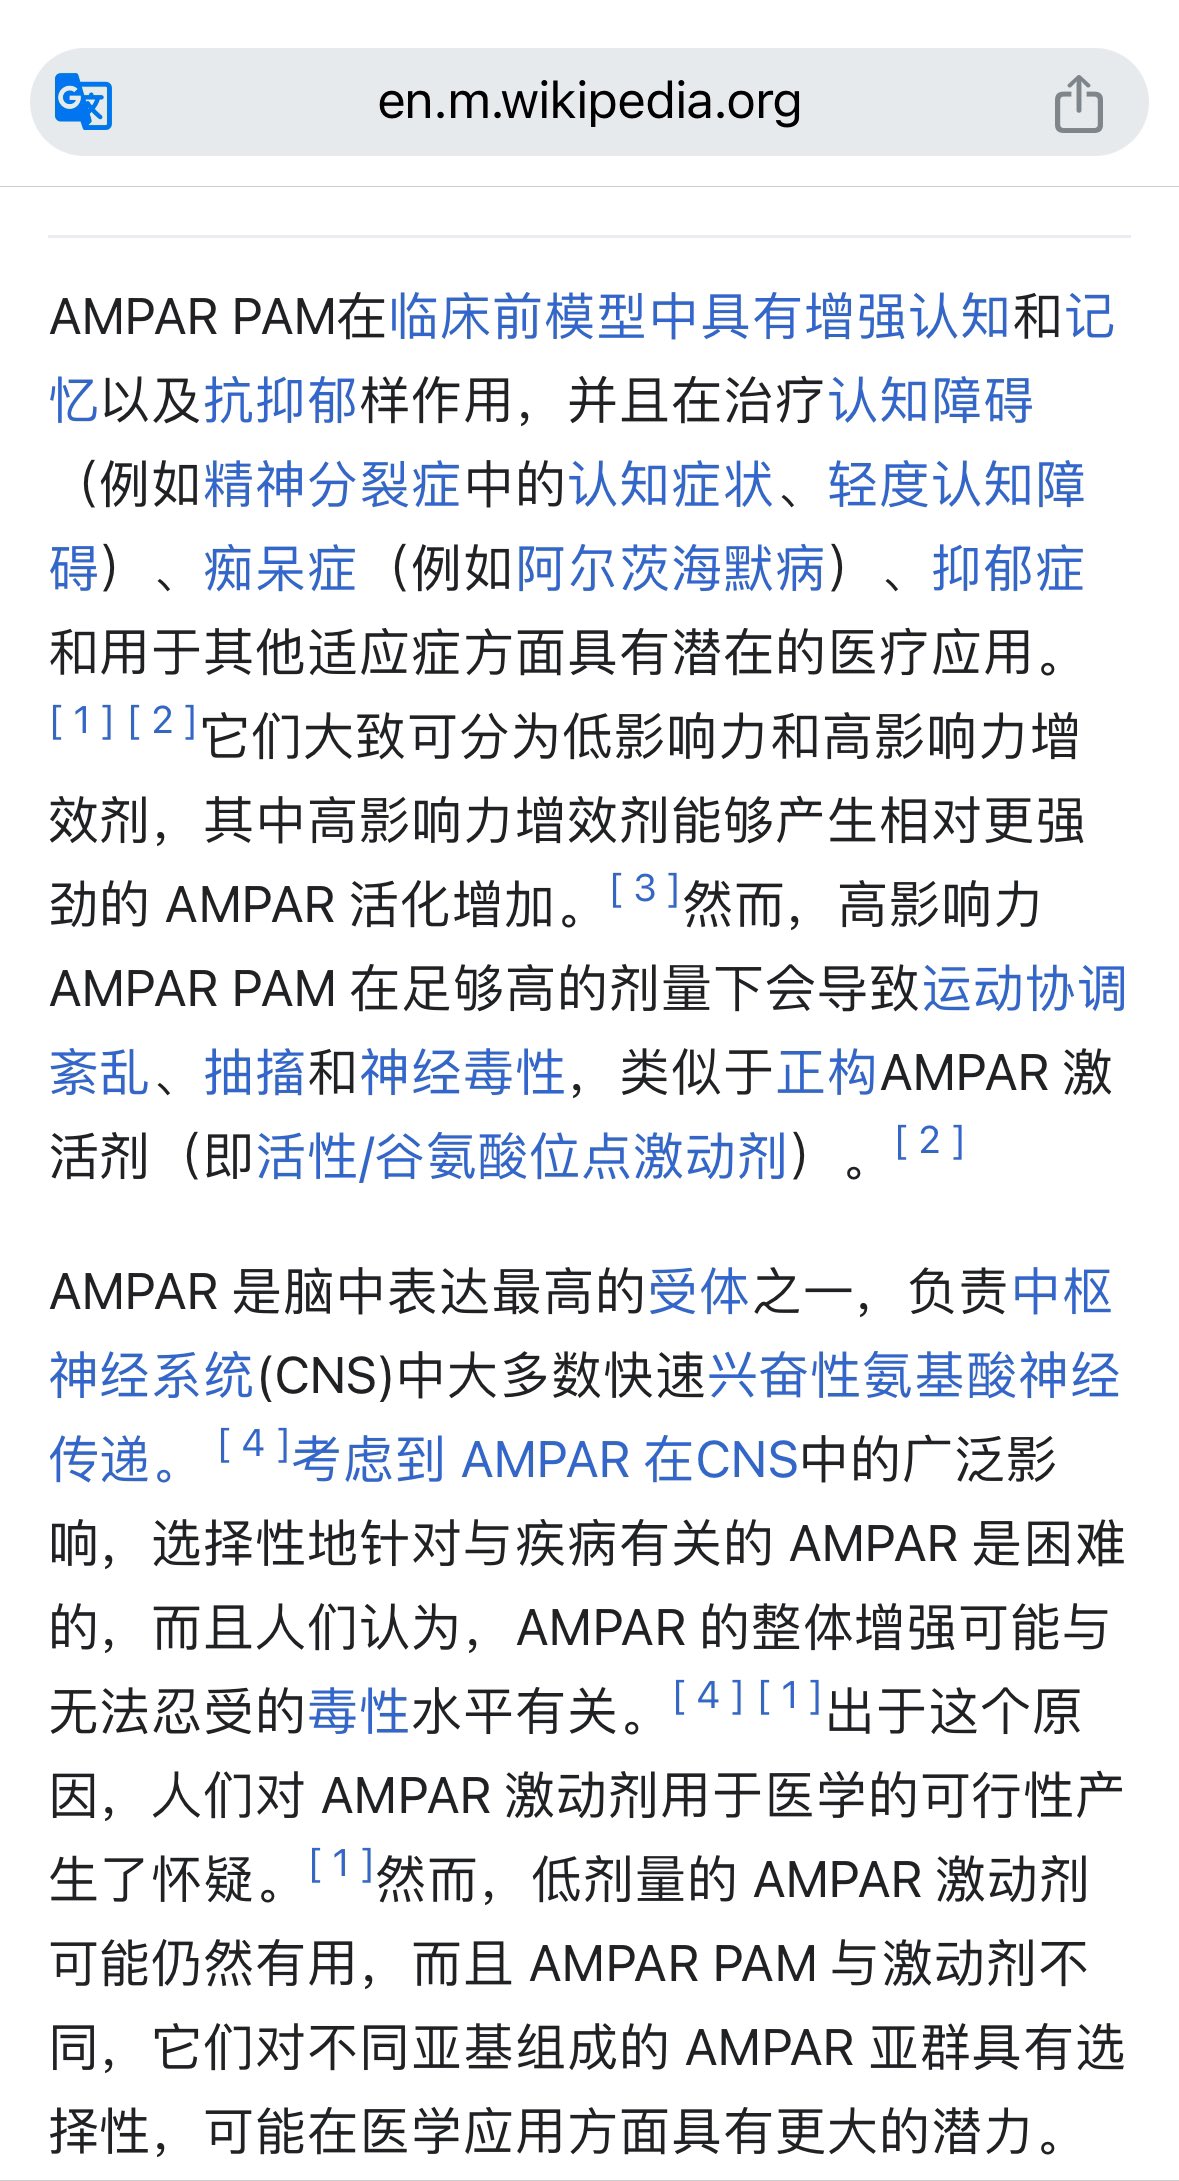

首先,从定义上讲,“反解离(anti-dissociative)”并不是一个标准的医学术语或者广泛认同的药理学分类。在正规资料,比如医学文献、维基百科、精神药理学教科书中,目前并没有“反解离药物”这个正式概念。

看上去像是为了描述某类特定效应而创造的术语(可能是nmda受体活性增强),用来对抗因NMDA受体拮抗剂(比如氯胺酮、DXM、PCP等)引发的解离体验(dissociation)。

那么更常见的是将其归入认知增强剂(cognitive enhancers),特别是改善认知连接性(connectivity)和现实感知(reality testing)的类型。

但其实在药理学上,单纯用“受体激动剂”来逆转“受体拮抗剂”的效应,有时会导致过度激活。

对于NMDA受体而言,过强的NMDA活化本身就与兴奋性毒性(excitotoxicity)和精神病样症状(psychotomimetic effects)有关,比如谷氨酸风暴可以引发严重的焦虑、妄想、乃至癫痫。

也就是说,简单地“激动-解除拮抗”在中枢神经系统是很危险的做法,尤其是对于易感个体(如有精神分裂素质的人)。

科学的处理方式一般是通过更细致的调节,比如微调NMDA/AMPA平衡、调节其他辅助途径(如GABA、5-HT、mGluR受体),而不是简单粗暴地用“NMDA增强剂”去顶回去。

而临床处理药物中毒中,其实医生更常用的做法是保守、支持性的治疗,比如补液,促进代谢,必要时镇静,以及监测生命体征防治并发症。

药物拮抗与受体激动之间,往往牵扯到的是复杂的适应性变化(receptor upregulation/downregulation),

不是简单的“给多一点刺激就能抵消”的关系